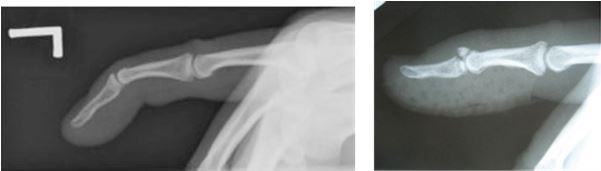

X-ray to confirm if the mallet finger is a bony or tendon injury.